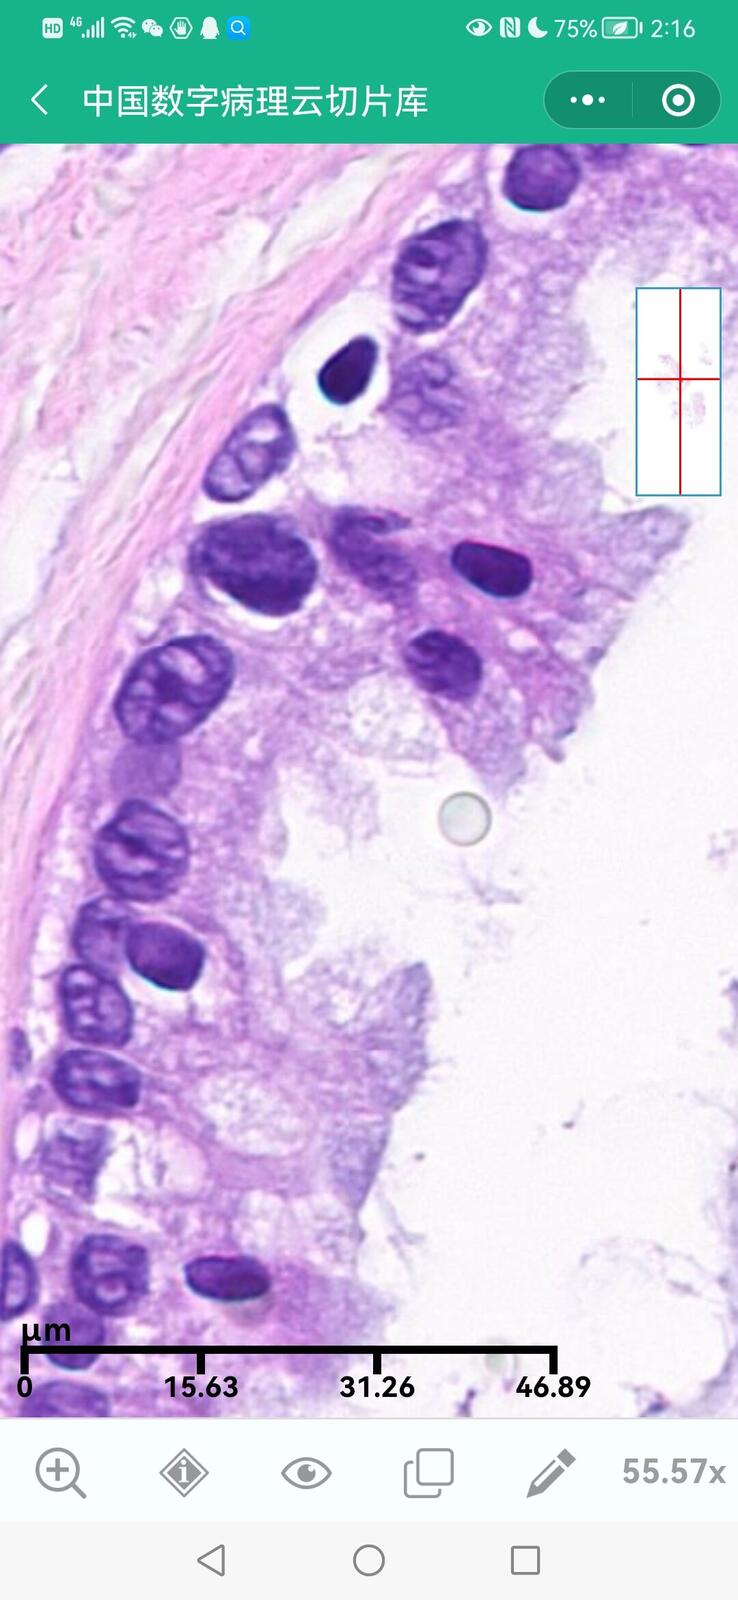

乳腺黏液性囊腺瘤伴导管内癌